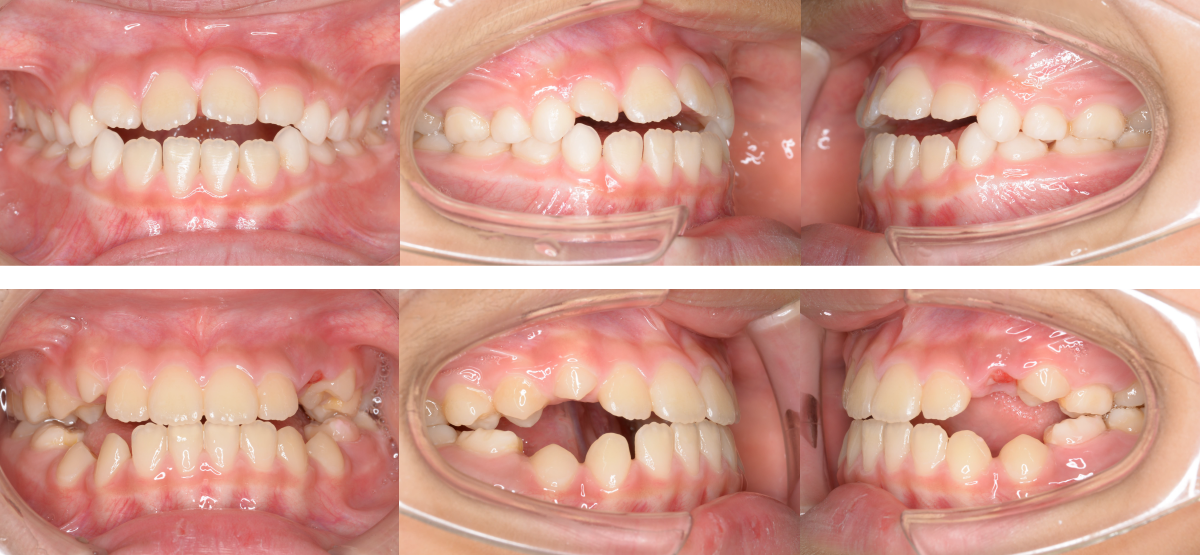

①子供(小児)の開咬の矯正治療例(7歳女児・治療期間1年3か月)

| 年齢・性別 | 7歳女児 |

| 治療期間 | 1年3か月 |

| 抜歯 | なし |

| 治療費 | 37万円(調整費、保定費まで含む総額制) |

| 備考 | インビザラインファースト |

| リスク・副作用 | 痛み・治療後の後戻り・歯根吸収・歯髄壊死・歯肉退縮 |

治療法は小児矯正(子供矯正)で、治療期間は1年3か月です。

上下顎の側方拡大を行い開咬の治療を行いました。

側方歯交換まで経過観察が必要です。